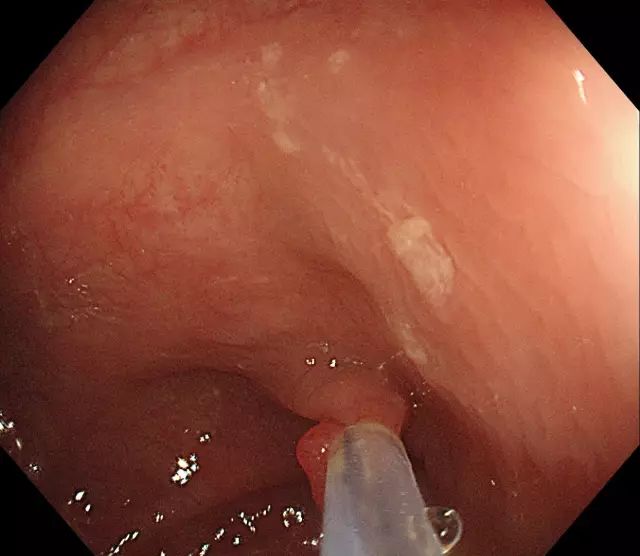

步骤二:通过肠镜上的孔道插入特殊器械(电圈套器),并在息肉旁伸出钢丝圈。

图片

步骤三:将钢丝圈套住息肉,并于息肉根部收紧钢丝圈。